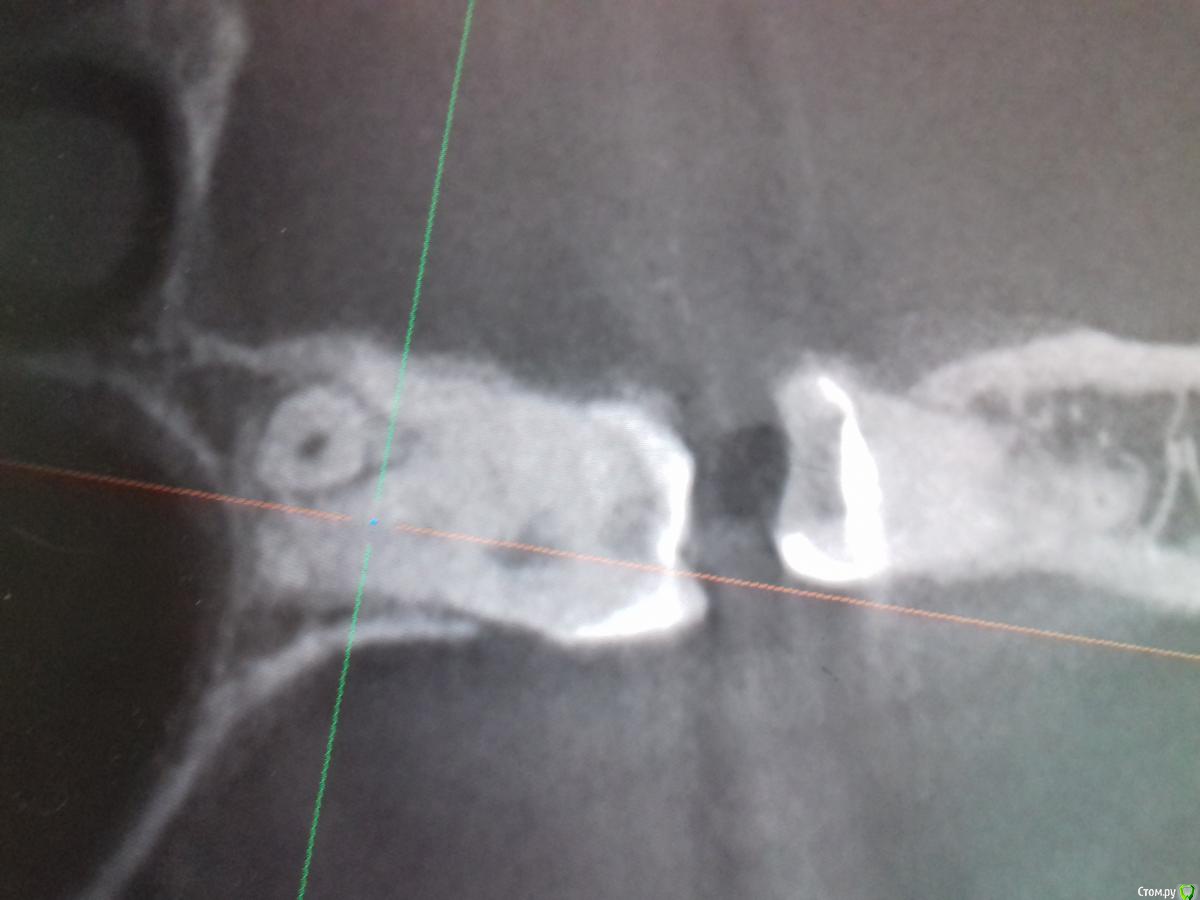

Jurai Опубликовано 29 декабря, 2016 Поделиться Опубликовано 29 декабря, 2016 А эта восьмерка спряталась лучше всех 1 Ссылка на комментарий

diesel87 Опубликовано 30 декабря, 2016 Поделиться Опубликовано 30 декабря, 2016 А эта восьмерка спряталась лучше всехIMG-20161228-WA0002.jpegIMG-20161228-WA0006.jpegIMG-20161228-WA0004.jpegСерьезно легла, убирать будете? Ссылка на комментарий

Jurai Опубликовано 30 декабря, 2016 Поделиться Опубликовано 30 декабря, 2016 А зачем, это случайная находка. Пусть лежит. 1 Ссылка на комментарий